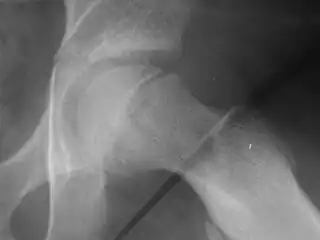

| X-ray showing a slipped capital femoral epiphysis, before and after surgical fixation. | |

The diagnosis requires x-rays of the pelvis, with anteriorposterior (AP) and frog-leg lateral views.[12] The appearance of the head of the femur in relation to the shaft likens that of a "melting ice cream cone", visible with Klein's line. The severity of the disease can be measured using the Southwick angle.

Slipped capital femoral epiphysis before surgery -

Xray showing SCFE